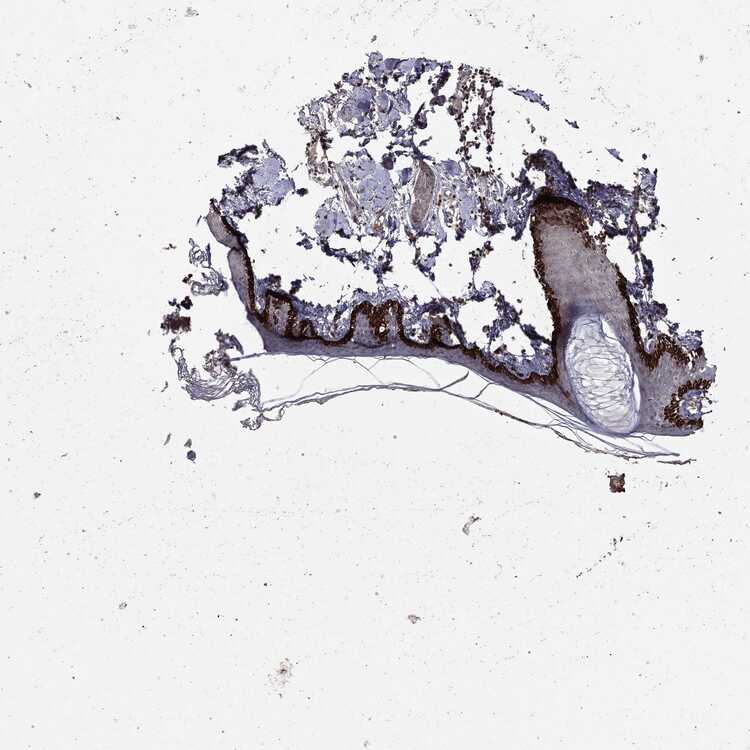

SKIN 1 - Antibody stainingi

Antibody staining in the annotated cell types in the current human tissue is reported as not detected, low, medium, or high, based on conventional immunohistochemistry profiling in selected tissues. This score is based on the combination of the staining intensity and fraction of stained cells.

Each image is clickable and will lead to virtual microscopy that enables deeper exploration of all samples and also displays staining intensity scores, fraction scores and subcellular localization as well as patient and tissue information for each sample.

Antibody CAB069425Antibody CAB080053Antibody CAB080065Antibody CAB080070Antibody CAB080081Antibody CAB080095Antibody CAB080097

Langerhans Not detectedNot detectedMediumNot detectedNot detectedNot detectedNot detected

Fibroblasts Not detectedNot detectedMediumMediumNot detectedMediumNot detected

Keratinocytes MediumMediumLowNot detectedNot detectedLowNot detected

Melanocytes Not detectedHighNot detectedMediumNot detectedMediumMedium